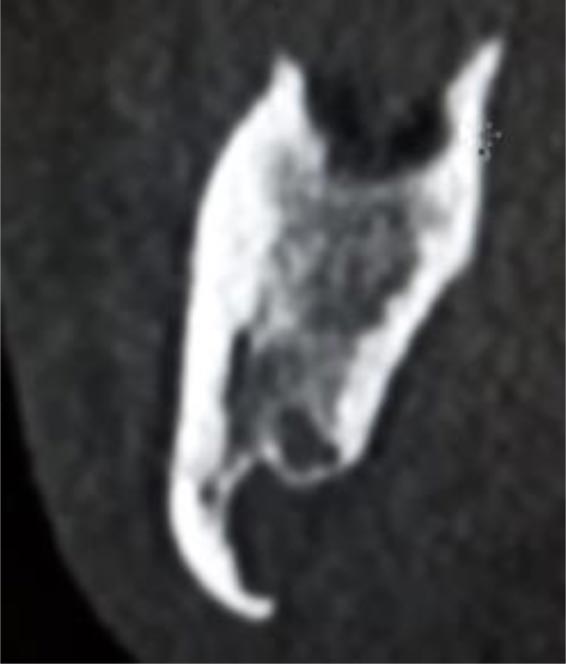

In this radiographic exam, we found an oval notch with radiolucent, clear and regular borders, located in the inferior portion of the horizontal branch of the mandible, on the lingual side, near the angle of the mandible, and below the mandibular canal. The X-ray allowed precise measurement showing a height ranging between 13.5 mm and 17 mm and breadth between 6 and 8 mm (Figs. 4-5).

The bi-dimensional reconstructions in parasagittal slices also permitted better identification of the closeness of the bone cavity to the canal of the alveolar inferior omolateral nerve, whereas the computerized volume rendering offered a more accurate view of the surrounding anatomical features (Figs. 6-12).